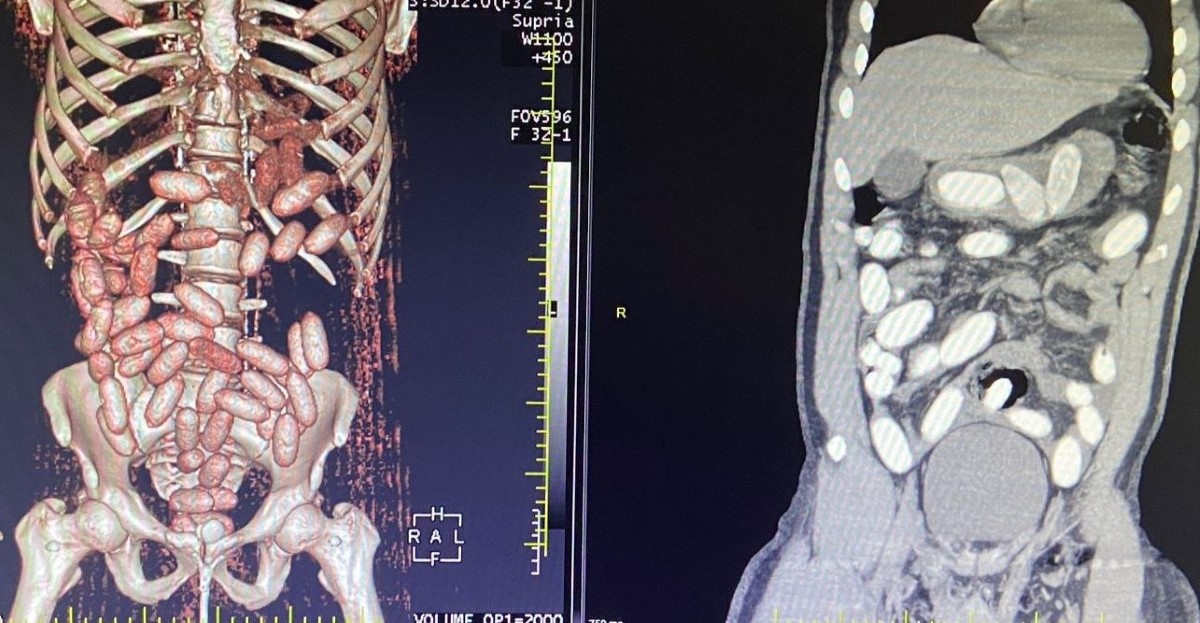

Gümrük Muhafaza Ekiplerince savcılık talimatı doğrultusunda detaylı bilgisayar tomografi çekilmesi için sağlık kuruluşuna götürülen 6 yolcunun yapılan tarama ve muayenelerinde 761 adet ve toplam ağırlığı 10 kilo 420 gram kokain tespit edildi. İkinci gerçekleştirilen operasyonda, başka bir yolcunun da yutucu kurye olduğu bilgisine ulaşan ekipler şüpheli şahsı takibe aldı.

Bahse konu yolcuda, yutucu tespit cihazı ve akabinde sağlık kuruluşunda yapılan muayene sonucunda 48 adet kapsül ve toplam ağırlığı 760 gram kokain ele geçirildi.